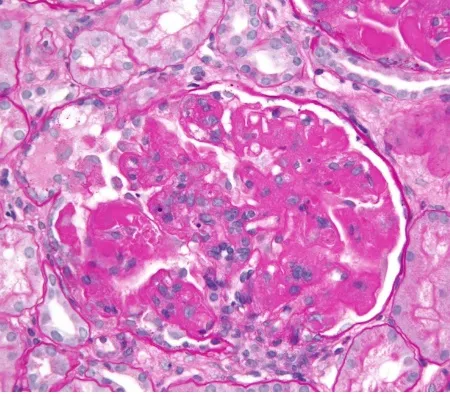

A hemodiafiltração pode aumentar significativamente a depuração de diversos medicamentos, levando a subdosagem quando usamos protocolos baseados em hemodiálise convencional. Entender a farmacocinética da droga e a prescrição da HDF é essencial para evitar falha terapêutica e ajustar corretamente as doses.